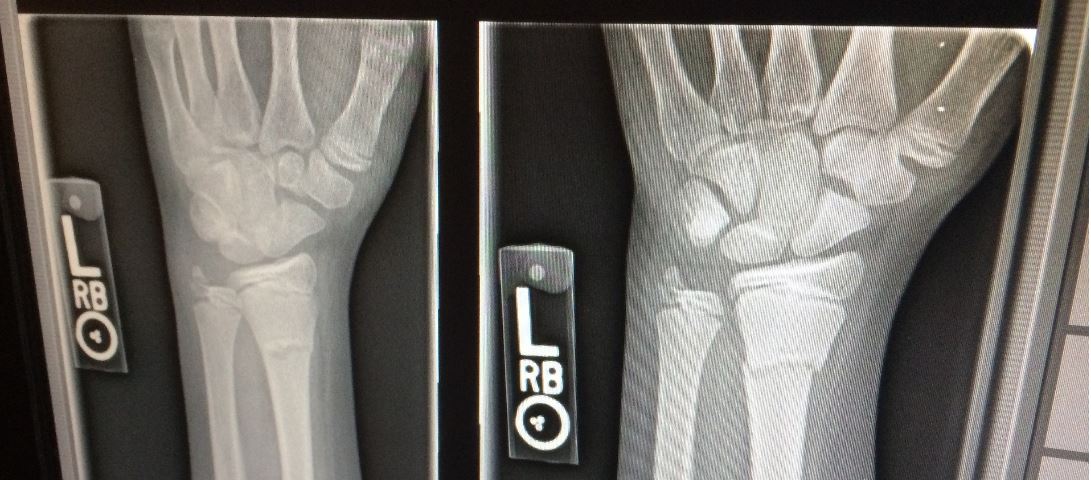

A novel way to pinpoint and illuminate bone damage promises to make X-rays more efficient at diagnosing bone and other injuries, Flinders University researchers say. The new technique, looking at potential biomedical applications of an ancient inorganic salt-based aggregation induced emission (AIE) radio-luminescence material, could open new frontiers in medicine including X-ray dosimetry, bioimaging and advanced applications such as optogenetics.

A novel way to pinpoint and illuminate bone damage promises to make X-rays more efficient at diagnosing bone and other injuries, Flinders University researchers say.

The new technique, looking at potential biomedical applications of an ancient inorganic salt-based aggregation induced emission (AIE) radio-luminescence material, could open new frontiers in medicine including X-ray dosimetry, bioimaging and advanced applications such as optogenetics, says Professor Youhong Tang, from Flinders University’s College of Science and Engineering.

“We were able to use Micro-X advanced X-ray machines at the Tonsley Innovation District to show the benefits of this AIEgen system which can be excited by X-ray (as the radioluminescence emitter) and UV light (as the photoluminescence emitter) compared to current AIEgens which mostly only act as the photoluminescence emitter,” he says.

“The study highlighted the disadvantages of autofluorescence, poor signal-to-noise radio, and poor tissue penetration depth of traditional photoluminescence emitters which could be elegantly solved by these radioluminescence luminogens,” says Professor of Mechanical and Materials Engineering, Dr Tang.

“Not only do they pinpoint bone and soft tissue damage for better diagnosis and treatment but we suggest further studies could see these AIE-based materials with multifunctionalities used for improved drug delivery, biosensors, bioimaging, and tissue engineering.”